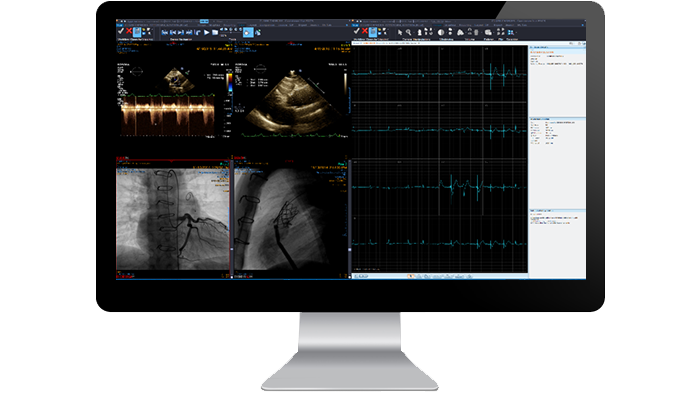

Cardiología

Proporcione un espacio de trabajo único y completo que agilice el acceso a las imágenes cardiológicas entre diferentes ubicaciones y modalidades para que el diagnóstico, la notificación, el almacenamiento y la distribución de los datos clínicos sean más rápidos. Nuestro sistema de archivado de imágenes basado en web integra la revisión de ecocardiografías, cateterismos cardiacos, ECG, cardiología nuclear y resultados de hemodinámica con la comparación sencilla de exámenes previos para mejorar el cuidado del paciente.

Simple

Utilice una estación de trabajo basada en web que apenas requiere espacio para todas sus necesidades cardiológicas.

Eficiente

Agilice los informes cardiológicos con plantillas estructuradas, mediciones completadas previamente y acceso integrado a imágenes desde diferentes modalidades y proveedores.

Unificado

Habilite la interpretación local o remota de datos cardiológicos desde cualquier estación de trabajo en red dentro y fuera del centro.

Funciones y ventajas

Revisión y análisis de TC cardiaca

Conjunto de herramientas para analizar los estudios de TC cardiaca integrado en la estación de trabajo de diagnóstico existente. Admite análisis de TC cardiaca, análisis coronario y cuantificación del calcio. Resulta fácil revisar la segmentación automática de los ejes del corazón (eje corto, eje largo, vista de cuatro cámaras), así como las capacidades de visualización monofásica y multifásica de diferentes proveedores. Las secuencias de cine, como volumen-cine o fase-cine, son compatibles.

Aplicación ECG Viewer

Aplicación integrada para analizar la forma de onda del ECG con un diseño de visualización de la derivación configurable. Admite la comparación con formas de onda de ECG anteriores, así como el uso de herramientas de medición como la línea y el calibrador.

Flujo de trabajo de revisión cardiovascular

Las herramientas de revisión y análisis cardiaco proporcionan vistas transversales del eje del corazón, vistas de cuatro cámaras y vistas panorámicas y transversales de las arterias cardiacas. El módulo de cuantificación del calcio le ayuda a analizar la placa calcificada, mientras que la función de eliminación de la caja oculta la anatomía no necesaria para la visualización cardiaca. La visualización de imágenes múltiples incluye imágenes de medicina nuclear, de ecografía y de angiografía.

Angiografía por sustracción digital

La sustracción digital mejora la visibilidad de los vasos sanguíneos en entornos de tejido óseo o denso. Aplicación incorporada para revisar la angiografía de rayos X diagnóstica e intervencionista y visualizar los vasos sanguíneos.